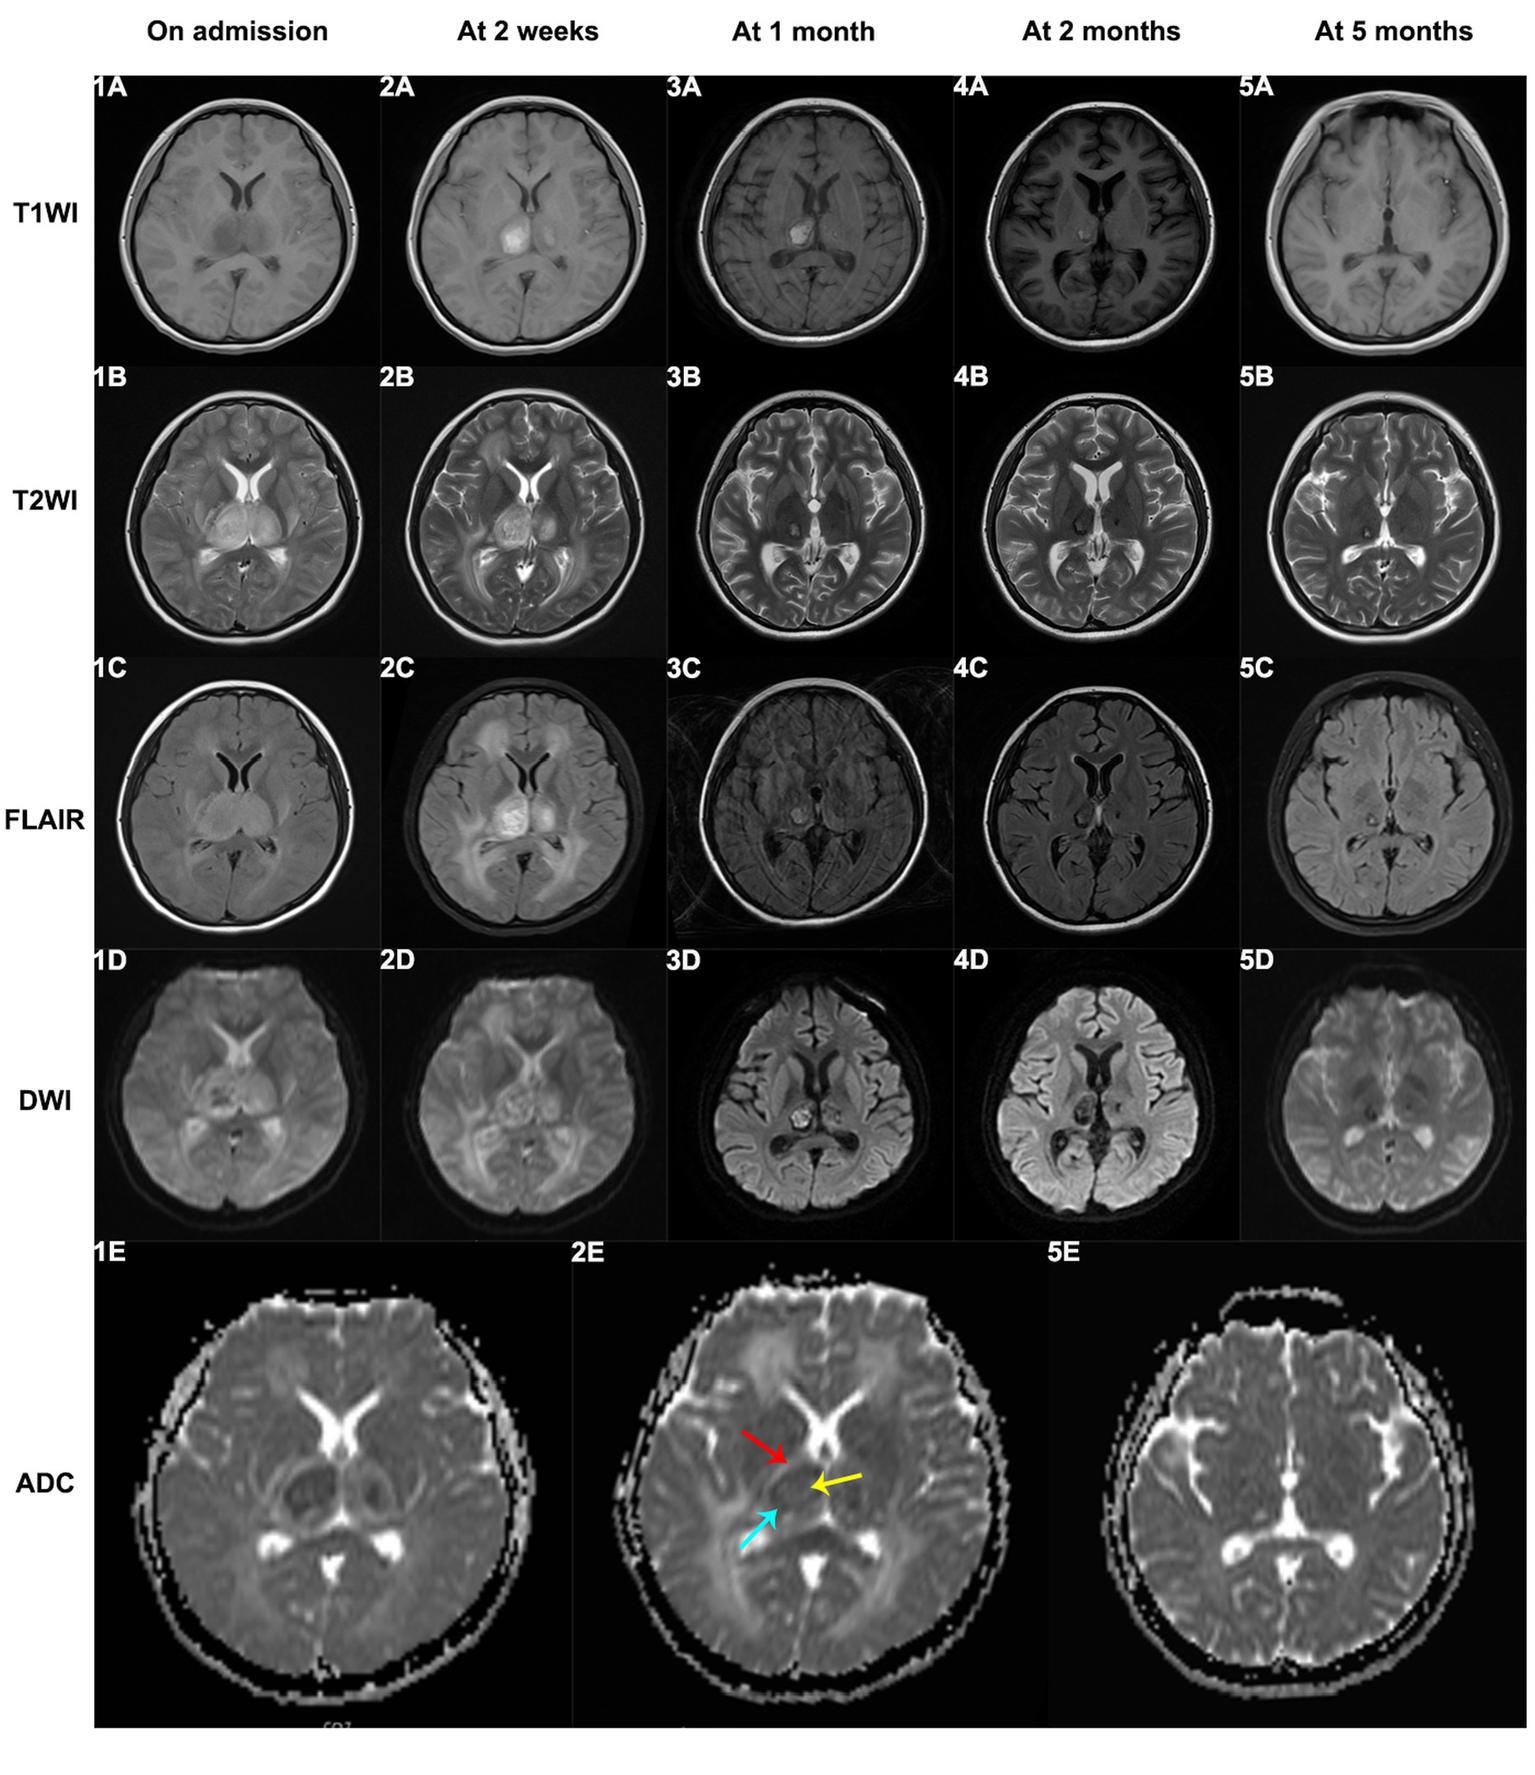

Sixteen patients underwent cerebrospinal fluid (CSF) examinations after admission. Most ANEC patients showed elevated protein content in the CSF, positive Pandy test, normal white blood cell count, normal chloride levels, and no decrease in glucose levels. Pathogen detection in the CSF was negative, indicating no direct evidence of pathogen invasion. Neuroimaging findings in ANEC patients exhibited symmetric thalamus involvement, involving other regions like the basal ganglia and brainstem. Figure 3 depicts the MRI changes of thalamic lesions throughout the disease in a 13-year-old female ANEC patient. Initially, the lesion area appeared isointense or slightly hypointense on T1-weighted imaging (T1WI), slightly hyperintense on T2-weighted imaging (T2WI) and fluid-attenuated inversion recovery (FLAIR) sequence, and heterogeneously hyperintense on diffusion-weighted imaging (DWI). The apparent diffusion coefficient (ADC) map displayed a typical concentric ring-shaped abnormal signal in the thalamus, with the outer layer showing a high signal indicating vascular edema, the middle layer showing a low signal indicating cytotoxic edema, and the inner layer showing slight elevation in ADC signal indicating hemorrhage and necrosis (9, 10). Most patients reached the peak of brain lesions around the second week of the disease course, with MRI indicating worsening cerebral hemorrhage and necrosis. After the acute phase, patients entered the recovery phase at 1 month, with older lesions being absorbed and MRI data suggesting old hemorrhagic lesions. Thalamic lesions showed significant regression at 2 and 5 months of follow-up, with MRI indicating iron deposition. Electroencephalogram (EEG) changes in ANEC patients were mainly characterized by background rhythm slowing, and some patients exhibited epileptic discharges. Bedside EEG monitoring showed bilateral cerebral hemisphere resting potentials with no response to stimulation in 5 cases.

Figure 3

The MRI changes of thalamic lesions throughout the disease in a 13-year-old female ANEC patient. Initially, the lesion area appeared isointense or slightly hypointense on T1WI, slightly hyperintense on T2WI and FLAIR sequence, and heterogeneously hyperintense on DWI. The ADC map displayed a typical concentric ring-shaped abnormal signal in the thalamus, with the outer layer showing a high signal indicating vascular edema (indicated by red arrow), the middle layer showing a low signal indicating cytotoxic edema (indicated by blue arrow), and the inner layer showing slight elevation in ADC signal indicating hemorrhage and necrosis (indicated by yellow arrow). T1WI, T1-weighted imaging; T2WI, T2-weighted imaging; FLAIR, fluid-attenuated inversion recovery; DWI, diffusion-weighted imaging; ADC, apparent diffusion coefficient.